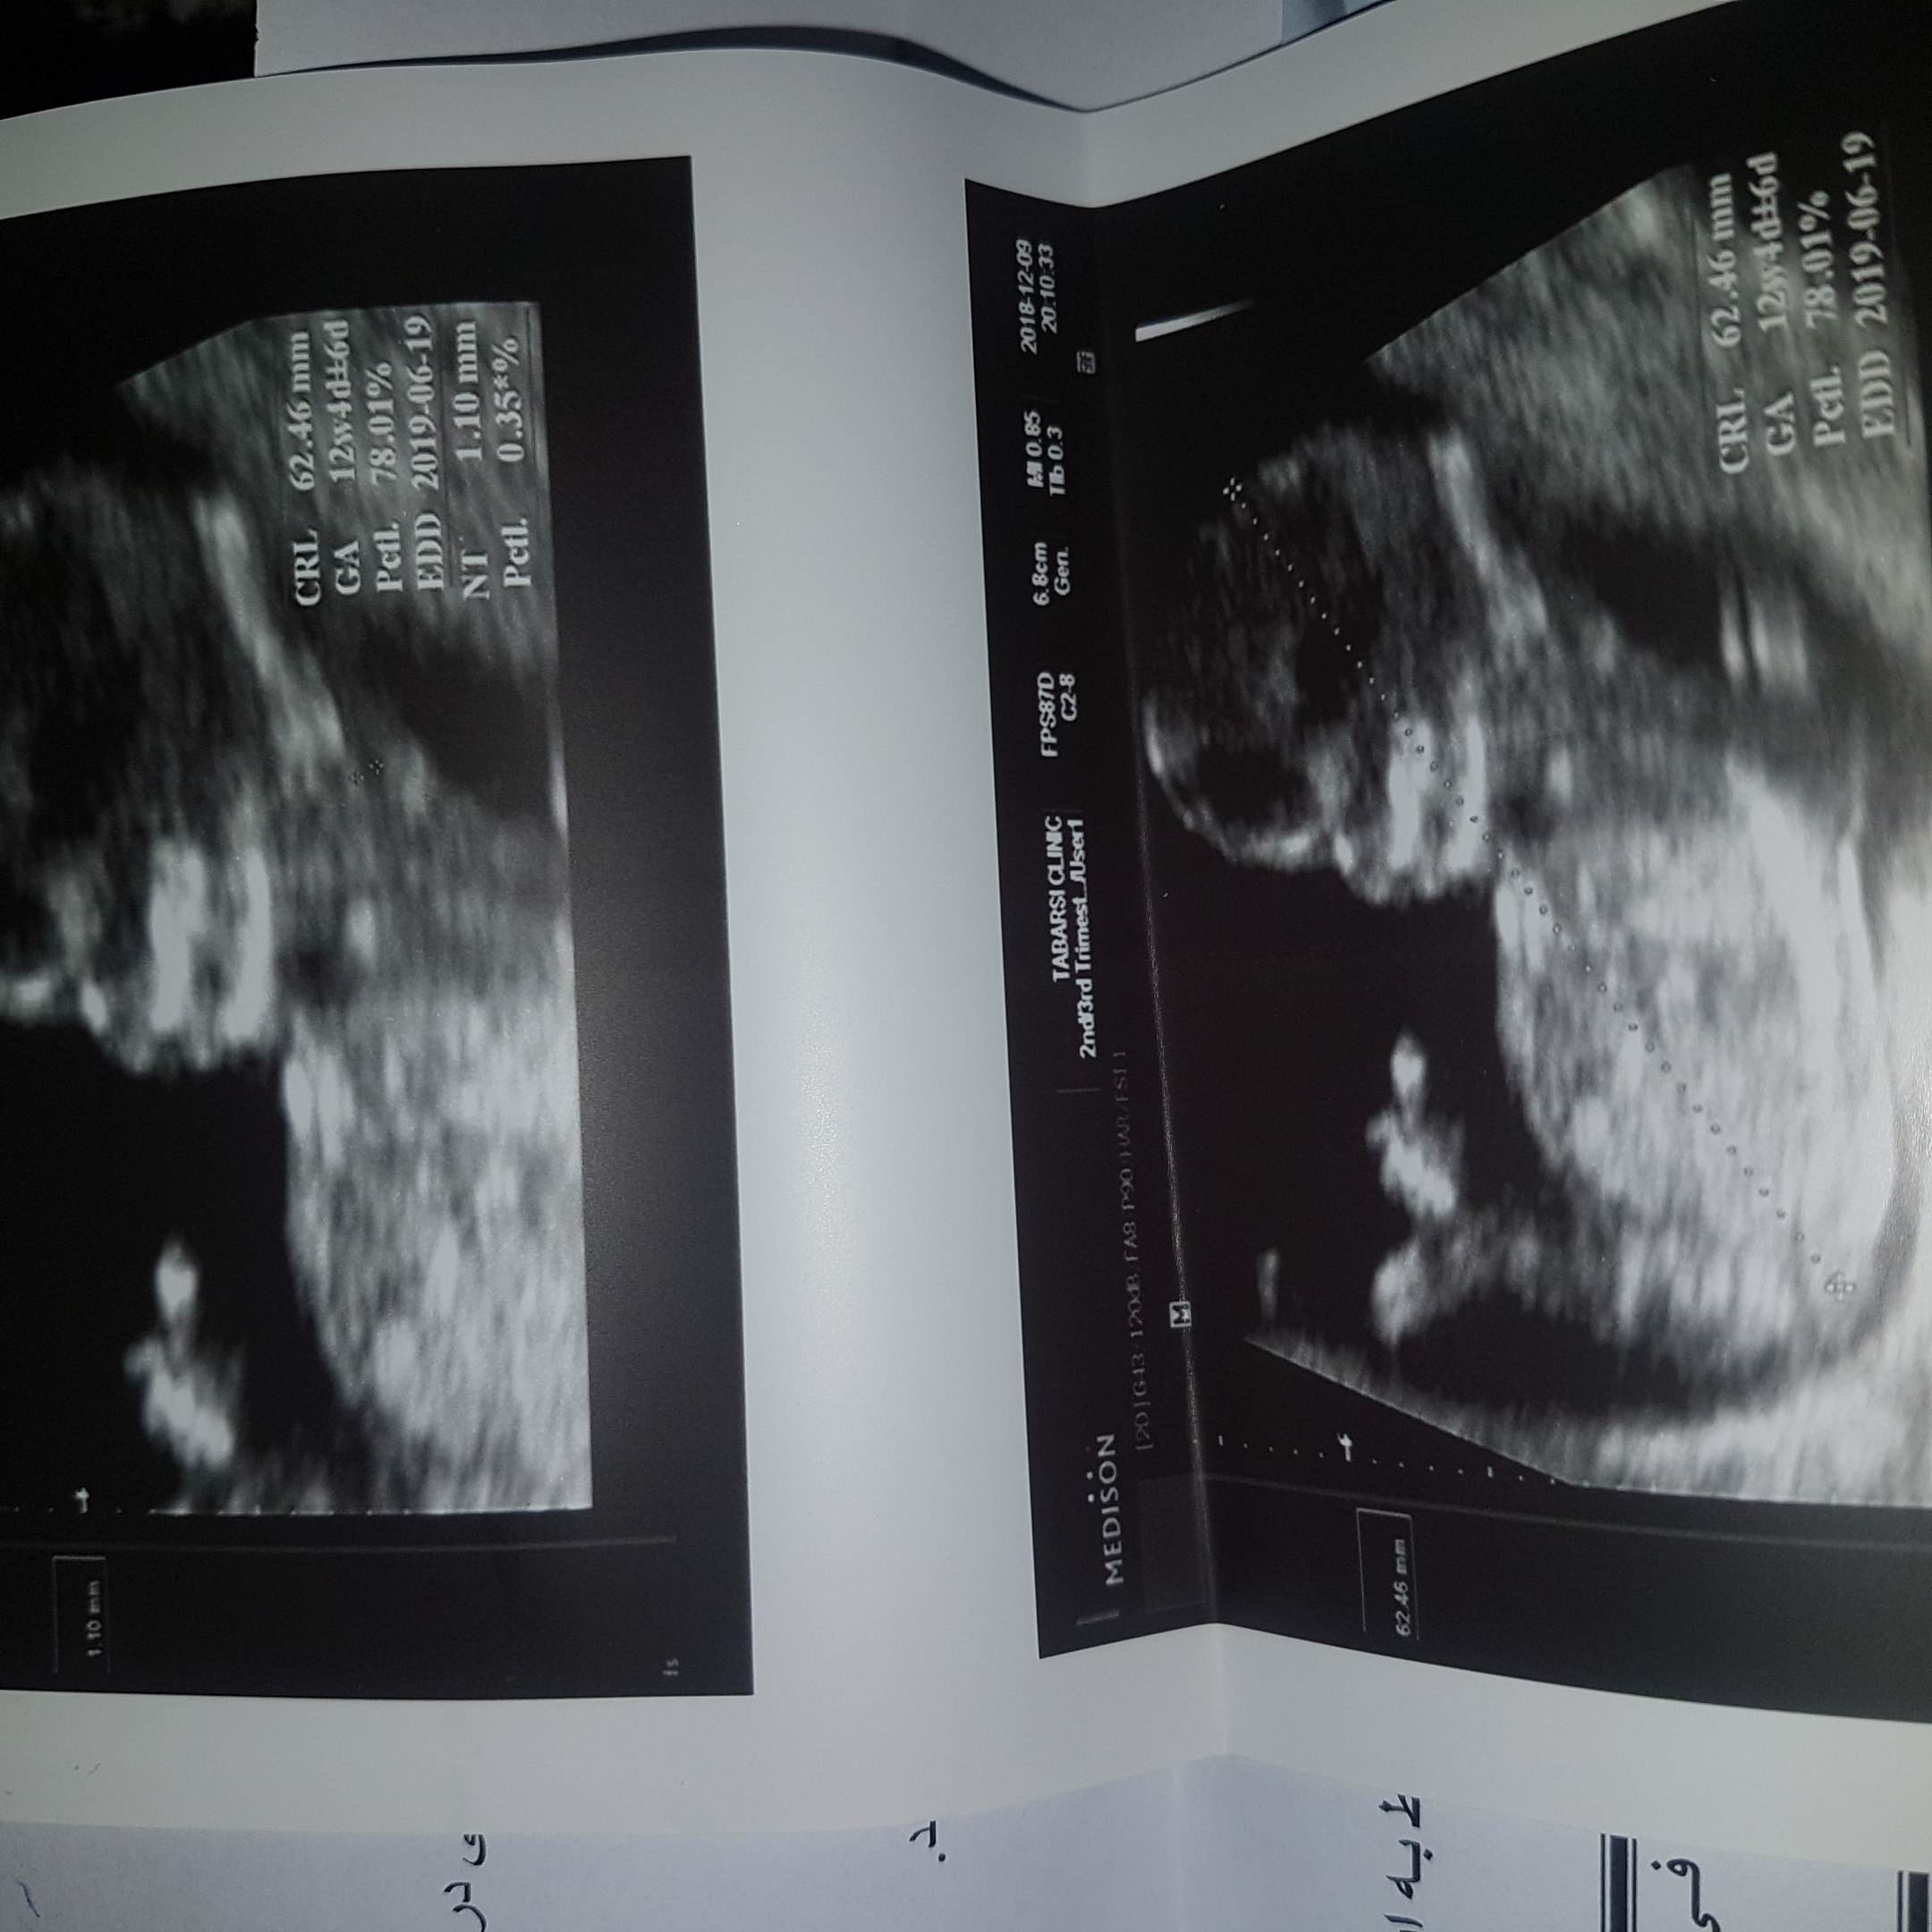

کسی می‌دونه شکل سر دختر و پسر  تو ان تی چه فرقی داره؟

دختر تیزه  پسر گرد

کجای سرش تیزه یا گرد؟